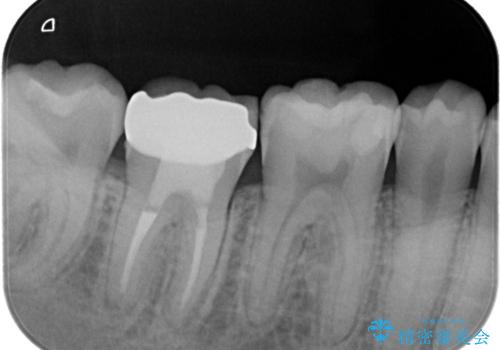

湾曲根管。精密根管治療

担当医 河口智英